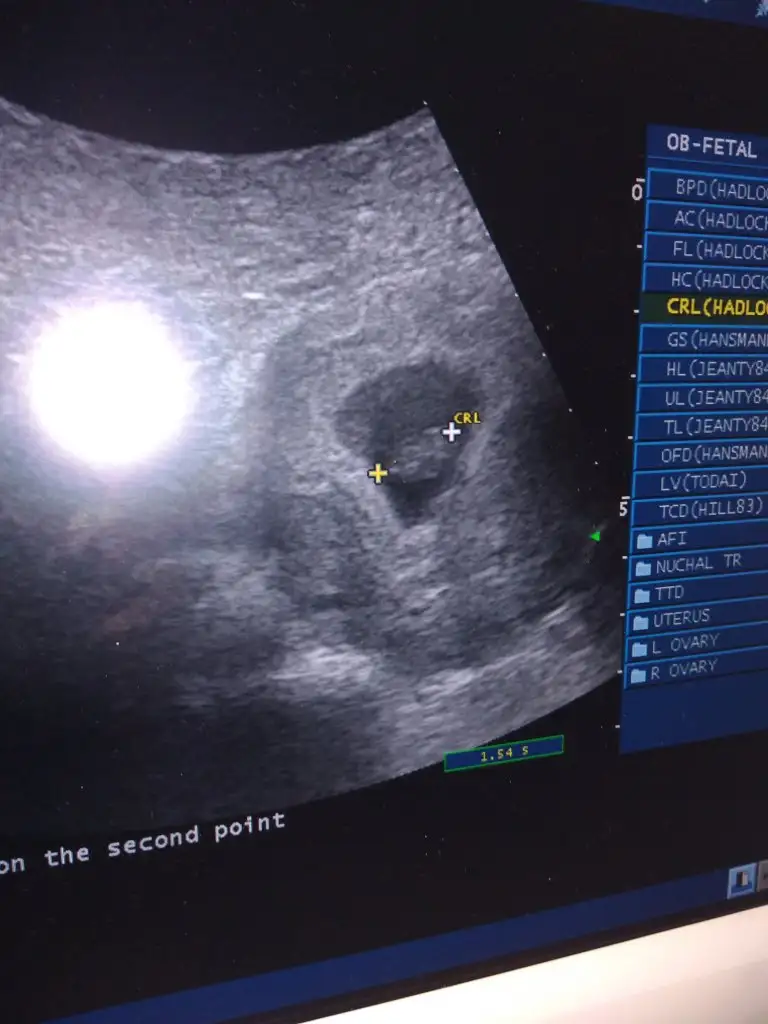

bnmde 5 +4 ken ultrasyonda baktırdım daha minik duruyodu benmki :)5+2 haftalık 14.44 mm yazıyo kağıtta

Canım bi bakar mısın ultrason fotoğrafımaKızlar bı arkadaş keseye göre tahmin yapıyor ve hep tutuyormuş iki oğlunu da bu şekilde cok yeniyken bile tahmin etmiş...ogullarinda kesesi hep uzunmuş muz gibi...yuvarlak ve yuvarlağa yakın olanlar hep kızdır diyor..ve bayağı emin konusuyor..benimki şişman bı fasulye gibi oo kesin kız görürsün dedi...sizlerin keselerinin şekli nasıldı ve cinsiyet neydi konusalimmi

burdaki sölenenlere göre kız gibi duruyor :))Kızlar tahmini olan var mı bildiğiniz fasulye gibi 6+4

6+4 de kese içindeki bebek görünüyo maşallah baya büyük bnmde bugun tam 6 hafta oldu cok merak ediyorum bu kadar büyümüşmüdür kalp atışlarıonı duyabildinizmiKızlar tahmini olan var mı bildiğiniz fasulye gibi 6+4